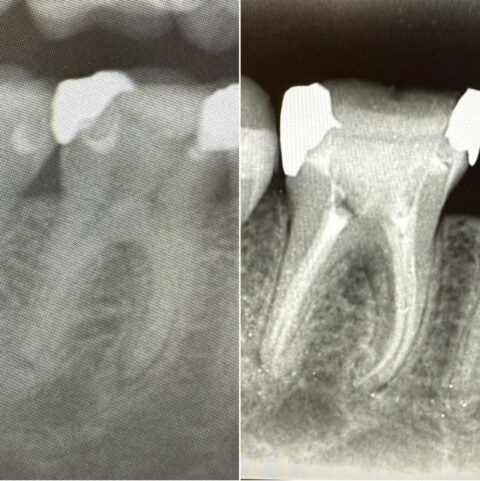

■他院で神経を取る治療を試みていたところ、激痛で麻酔が効かずに治療を中断された方が無痛リラクゼーション治療を希望され、当院にご来院されました。

泣くほど痛かったとのことで、歯科治療がトラウマになってしまいましたが、2回の無痛リラクゼーション治療で全く問題無く神経治療を終えました。

■4根管で細長く、軽度の湾曲があった為、ニッケルチタンファイルにて根管治療を行い、綺麗な充填が確認できます。

根管治療をしっかり行っても綺麗にお薬が充填されていないとまた菌が侵入して、再治療が必要な場合もあります。